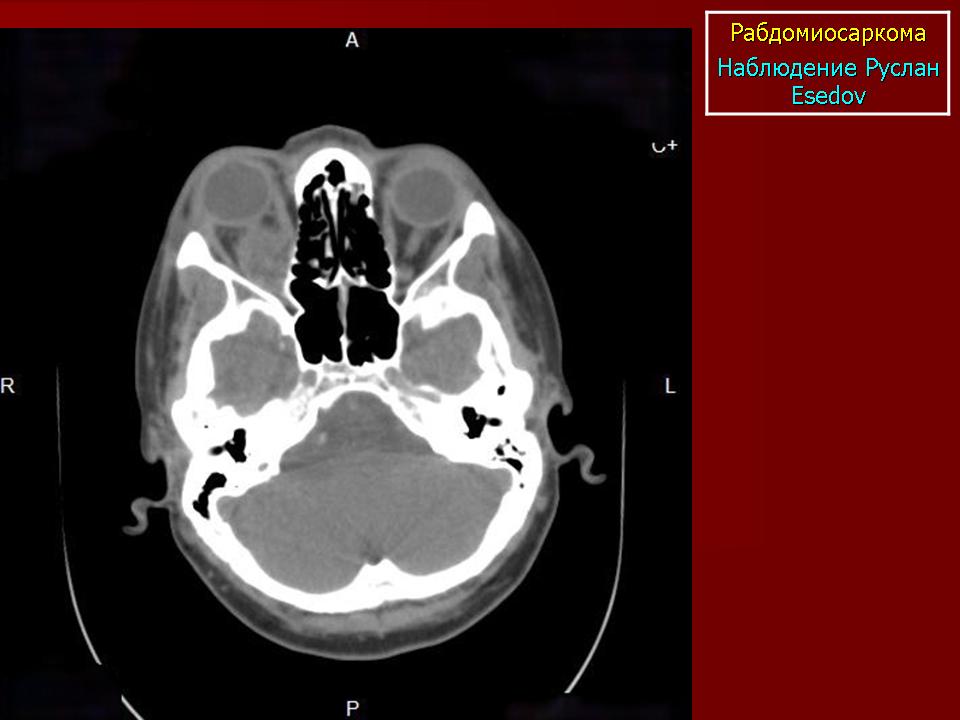

Рабдомиосаркома — чрезвычайно агрессивная опухоль орбиты, является наиболее частой причиной злокачественного роста в орбите у детей. Мальчики болеют почти в 2 раза чаще. Источником роста рабдомиосаркомы являются клетки скелетных мышц. Выделены три типа опухоли: эмбриональный, альвеолярный и плеоморфный, или дифференцированный. Последний тип встречается редко. У детей до 5 лет чаще развивается эмбриональный тип опухоли, после 5 лет — альвеолярный. Как правило, рабдомиосаркома состоит из элементов нескольких типов (смешанный вариант). Точный диагноз можно установить только на основании результатов электронной микроскопии.

Излюбленная локализация опухоли — верхневнутренний квадрант орбиты, поэтому в процесс рано вовлекаются мышца, поднимающая верхнее веко, и верхняя прямая мышца. Птоз, ограничение движений глаза, смещение его книзу и книзу кнутри — это первые признаки, на которые обращают внимание как сами больные, так и окружающие лица. У детей экзофтальм или смещение глаза при локализации опухоли в переднем отделе орбиты развивается в течение нескольких недель (рис. 20.23, а). У взрослых опухоль растет медленнее, в течение нескольких месяцев. Быстрое увеличение экзофтальма сопровождается появлением застойных изменений в эписклеральных венах, глазная щель полностью не смыкается, отмечаются инфильтраты на роговице и ее изъязвление. На глазном дне — застойный диск зрительного нерва. Первично развиваясь вблизи верхневнутренней стенки орбиты, опухоль быстро разрушает прилежащую тонкую костную стенку, прорастает в полость носа, вызывая носовые кровотечения. Ультразвуковое сканирование, компьютерная томография, термография и тонкоигольная аспирационная биопсия — это оптимальный диагностический комплекс инструментальных методов исследования при рабдомиосаркоме (рис. 20.23, б). Лечение комбинированное. Протокол лечения предусматривает предварительное проведение полихимиотерапии в течение 2 нед, после чего проводят наружное облучение орбиты. После комбинированного лечения более 3 лет живут 71 % больных.